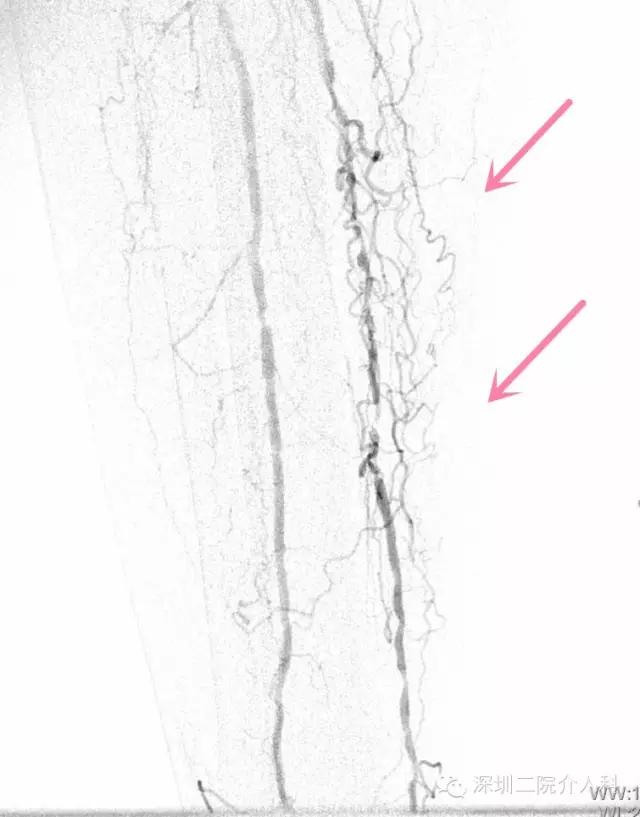

造影示右下肢胫后动脉、腓动脉造影多发狭窄闭塞: